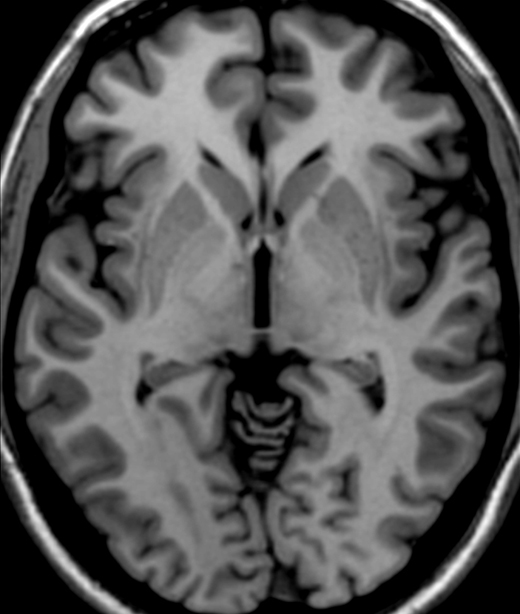

Within the "indirect pathway" of the basal ganglia, the striatum projects to this structure